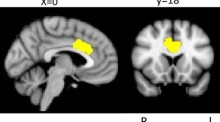

Regional gray matter density is associated with achievement motivation: evidence from voxel-based morphometry Hikaru TakeuchiYasuyuki TakiRyuta Kawashima Original Article Open access 05 December 2012 Pages: 71 - 83